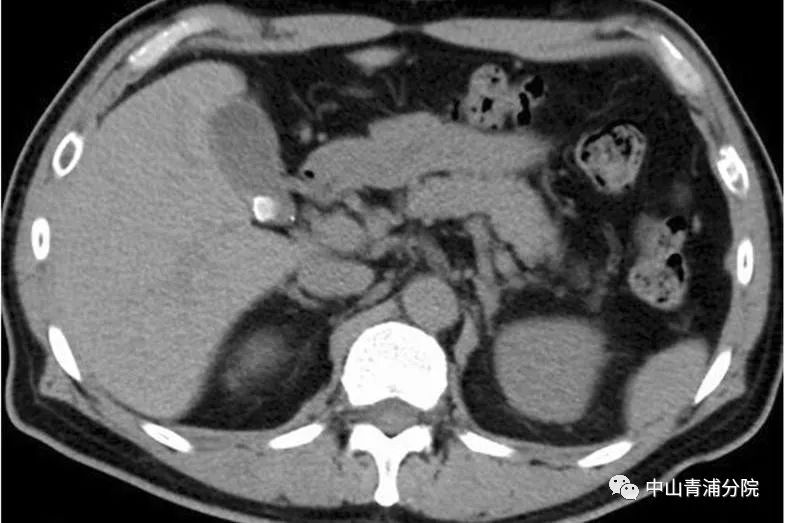

(胆囊结石CT表现)

患者往往有胆绞痛发作的病史,发作部位多位于上腹部或右上腹部,一般持续15分钟以上,疼痛可放射至右肩或后背,常伴有恶心或呕吐。大多数胆囊结石可以通过腹部B超、CT、内镜超声或磁共振胰胆管成像(MRCP)等明确诊断。